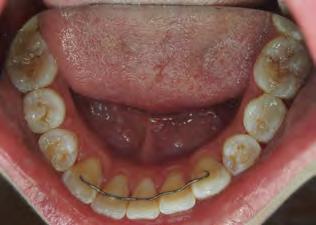

Two authors had access to the data and all information was de-identified. Study personnel made no contact with patients at any time throughout the study, and no PHI was recorded. Re corded data included diagnosis (clinical and/or pathologic), basic demographics (age, gender), and current prescription medica tions. For cases that were not biopsy-proven, the standard clinic protocol is that the clinical presentation must exhibit the charac teristic white Wickham striae for a patient to be given the clinical diagnosis of OLL or OLP (Figure 1). Any clinical diagnosis of OLL or OLP was rendered by one of four oral medicine experts in the Oral Medicine Clinic, and biopsy was performed in cases with any doubt.

Figure 1. Example of characteristic Wickham striae and reticular pattern on buccal mucosa used to clinically diagnose OLL and OLP cases. Erythematous areas also seen. Figure 2. Frequency and percent of study patients using specific medications with color-coded drug classes.